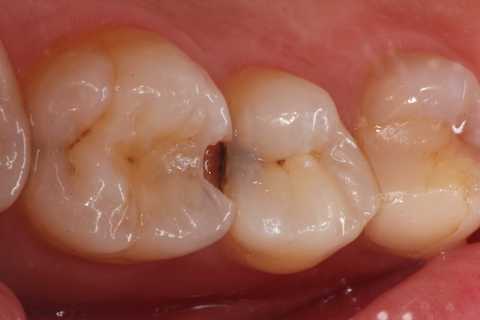

20代女性、右上6、咬合性外傷による隣接面カリエス

この歯は10年以上も削らずに様子を見ていたのだが、最近しみるようになったとかで、東京住まいだし、次帰れるのは年末か?コロナもあるし分からない、、ということなので、介入することにした。

クラックが気になるのだが、象牙質には広がっていないようだったので、このまま充填した。

隣の5番はエアブローでしみなかったので、そのままだ。

実像から